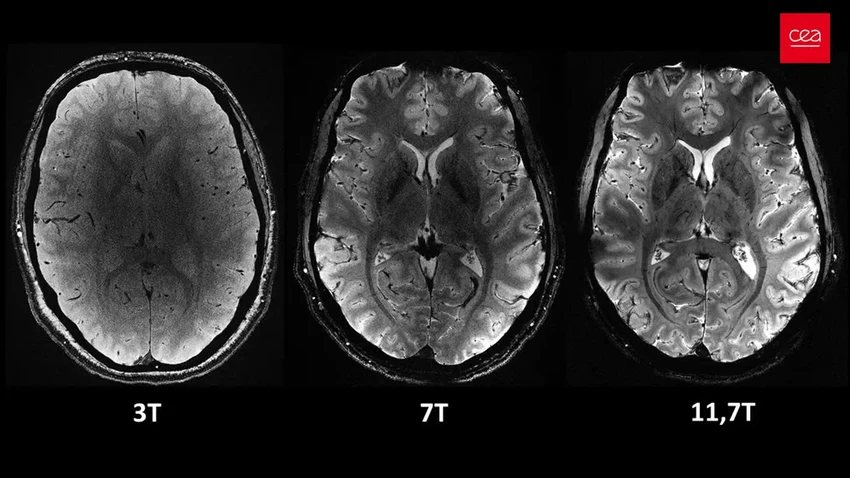

Созданный французскими учёными из комиссии CEA, этот титан генерирует магнитное поле невиданной силы — целых 11,7 Тесла. Для сравнения: обычный больничный томограф тянет на 1,5 или максимум 3 Тл. Чувствуете разницу? Это как сравнивать ручей с океанским течением.

Что это даёт? Фантастическую чёткость и скорость. Всего за четыре минуты Iseult делает снимки с разрешением до 0,2 мм по горизонтали, срезая слои толщиной в 1 миллиметр. На таком «срезе» умещаются тысячи нейронов одновременно. Удивительно, сколько информации можно собрать за время, пока вы завариваете чай, не правда ли?